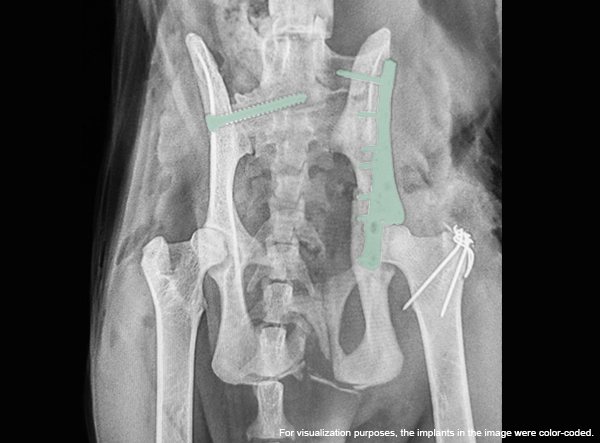

- LeiLOX 1.5 Y-Plate

Positioned on the ilium, the Y-Plate was used to stabilize the comminuted ilial fracture and restore acetabular alignment. The plate’s geometry allowed for secure multi-point fixation in challenging anatomy. - Twisted Straight Plate

A LeiLOX Locking 1.5 straight plate was carefully twisted and adapted to the curved contour of the ilium, providing additional stabilization of the ilial shaft. - Single Transarticular SI Screw

On the contralateral ilium (left side), a long cortical screw was placed across the SI joint into the sacrum to address the sacroiliac luxation. This achieved rigid fixation of the pelvis to the vertebral column.

Post-operative radiographs showed excellent alignment, secure implant positioning, and stable SI fixation. This multifaceted repair highlights the versatility of the LeiLOX system and the skill of the surgical team. The patient is recovering well with a positive long-term prognosis.